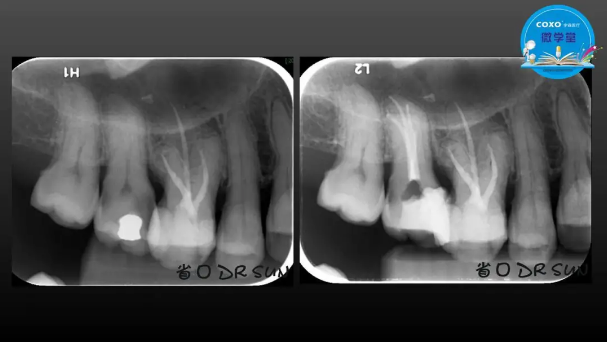

主講:孫書昱

主任醫(yī)師,牙體牙髓副主任, 廣東省口腔醫(yī)院牙體牙髓科 主任醫(yī)師。2003年碩士研究生畢業(yè),研究方向?yàn)檠荔w牙髓病學(xué),擅長(zhǎng)于牙體牙髓病的診斷、齲齒、牙髓炎、根尖周病的治療以及前牙美容修復(fù)。